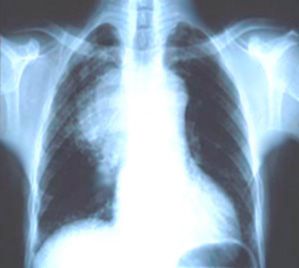

Chest films obtained at the primary medical facility showed a mass in the right lung field (Figure). MRI and CT scans of the head had found no abnormalities. CT scan of the chest revealed an incidental mediastinal mass. Bronchoscopic biopsy revealed limited-stage small-cell lung cancer (SCLC).

Figure.